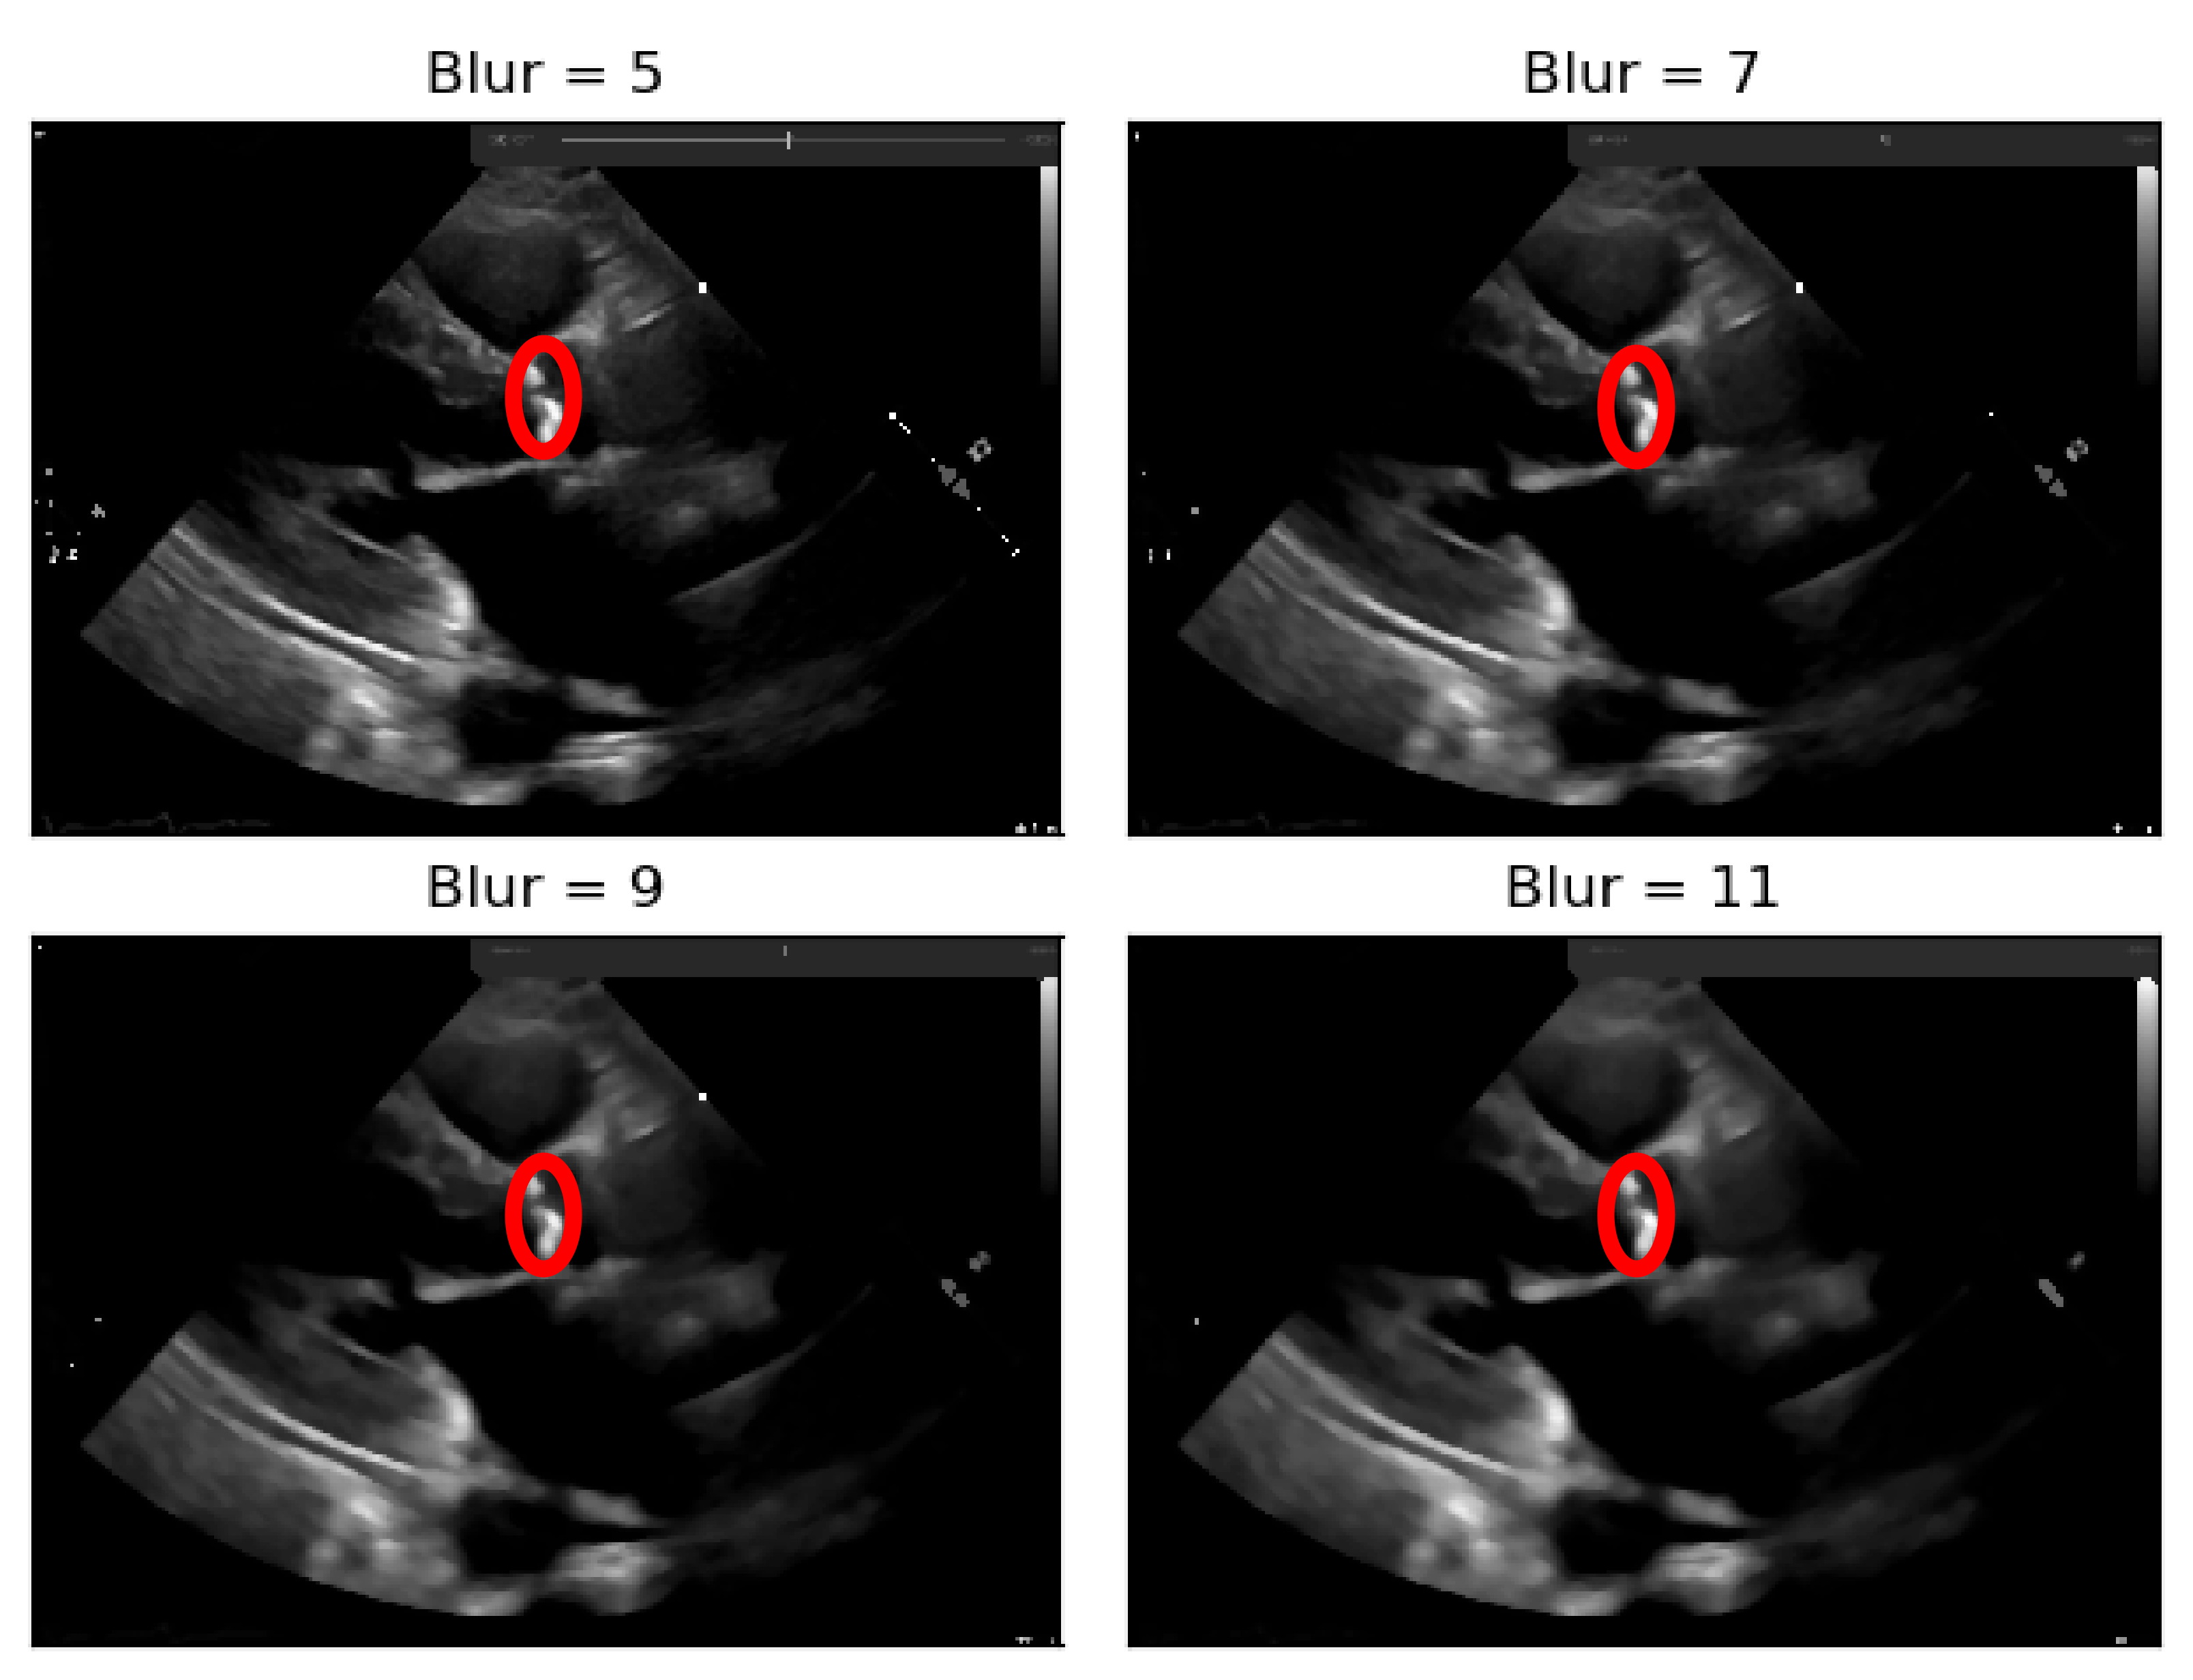

To the resulting images of this blurring phase, a binarization operation with a fixed pixel threshold value of 160 was produced, experimentally obtained by analyzing 48 cases of echocardiography images, where 255 corresponds to calcium, as seen in Figure 5. This initial approach of a using a fixed threshold is not sufficient for our problem at hand, since our images’ brightness may vary, given different data collection conditions. To tackle this issue, an adaptive binarization technique has to be performed, which will be further explained.

In Figure 5, it is noticeable that when the blurring parameter increases from 5 to 11, we get a cleaner image (without small white dots—noise). However, we can also notice that in the region of interest (marked with red circles), when the blur increases, we lose pixels, since the region gets smaller. To mitigate this, a mask dilation operator was applied to each region of interest.

Figure 5. Binarization of an echocardiography image, for each size of the kernel parameter applied—The red circle represents our ROI (aortic valve).